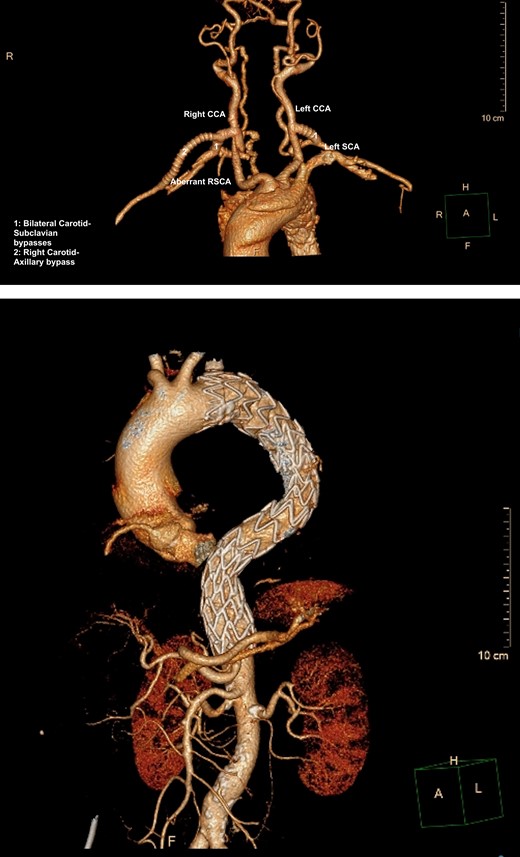

A 61-year-old male presented to a peripheral hospital emergency department with a 12-hour history of central chest pain with onset during sexual activity. He was an active smoker with poorly controlled essential hypertension. CT angiography showed an IMH from the left common carotid artery origin to the distal descending thoracic aorta, also involving the proximal ARSA and KD (Fig. 3).